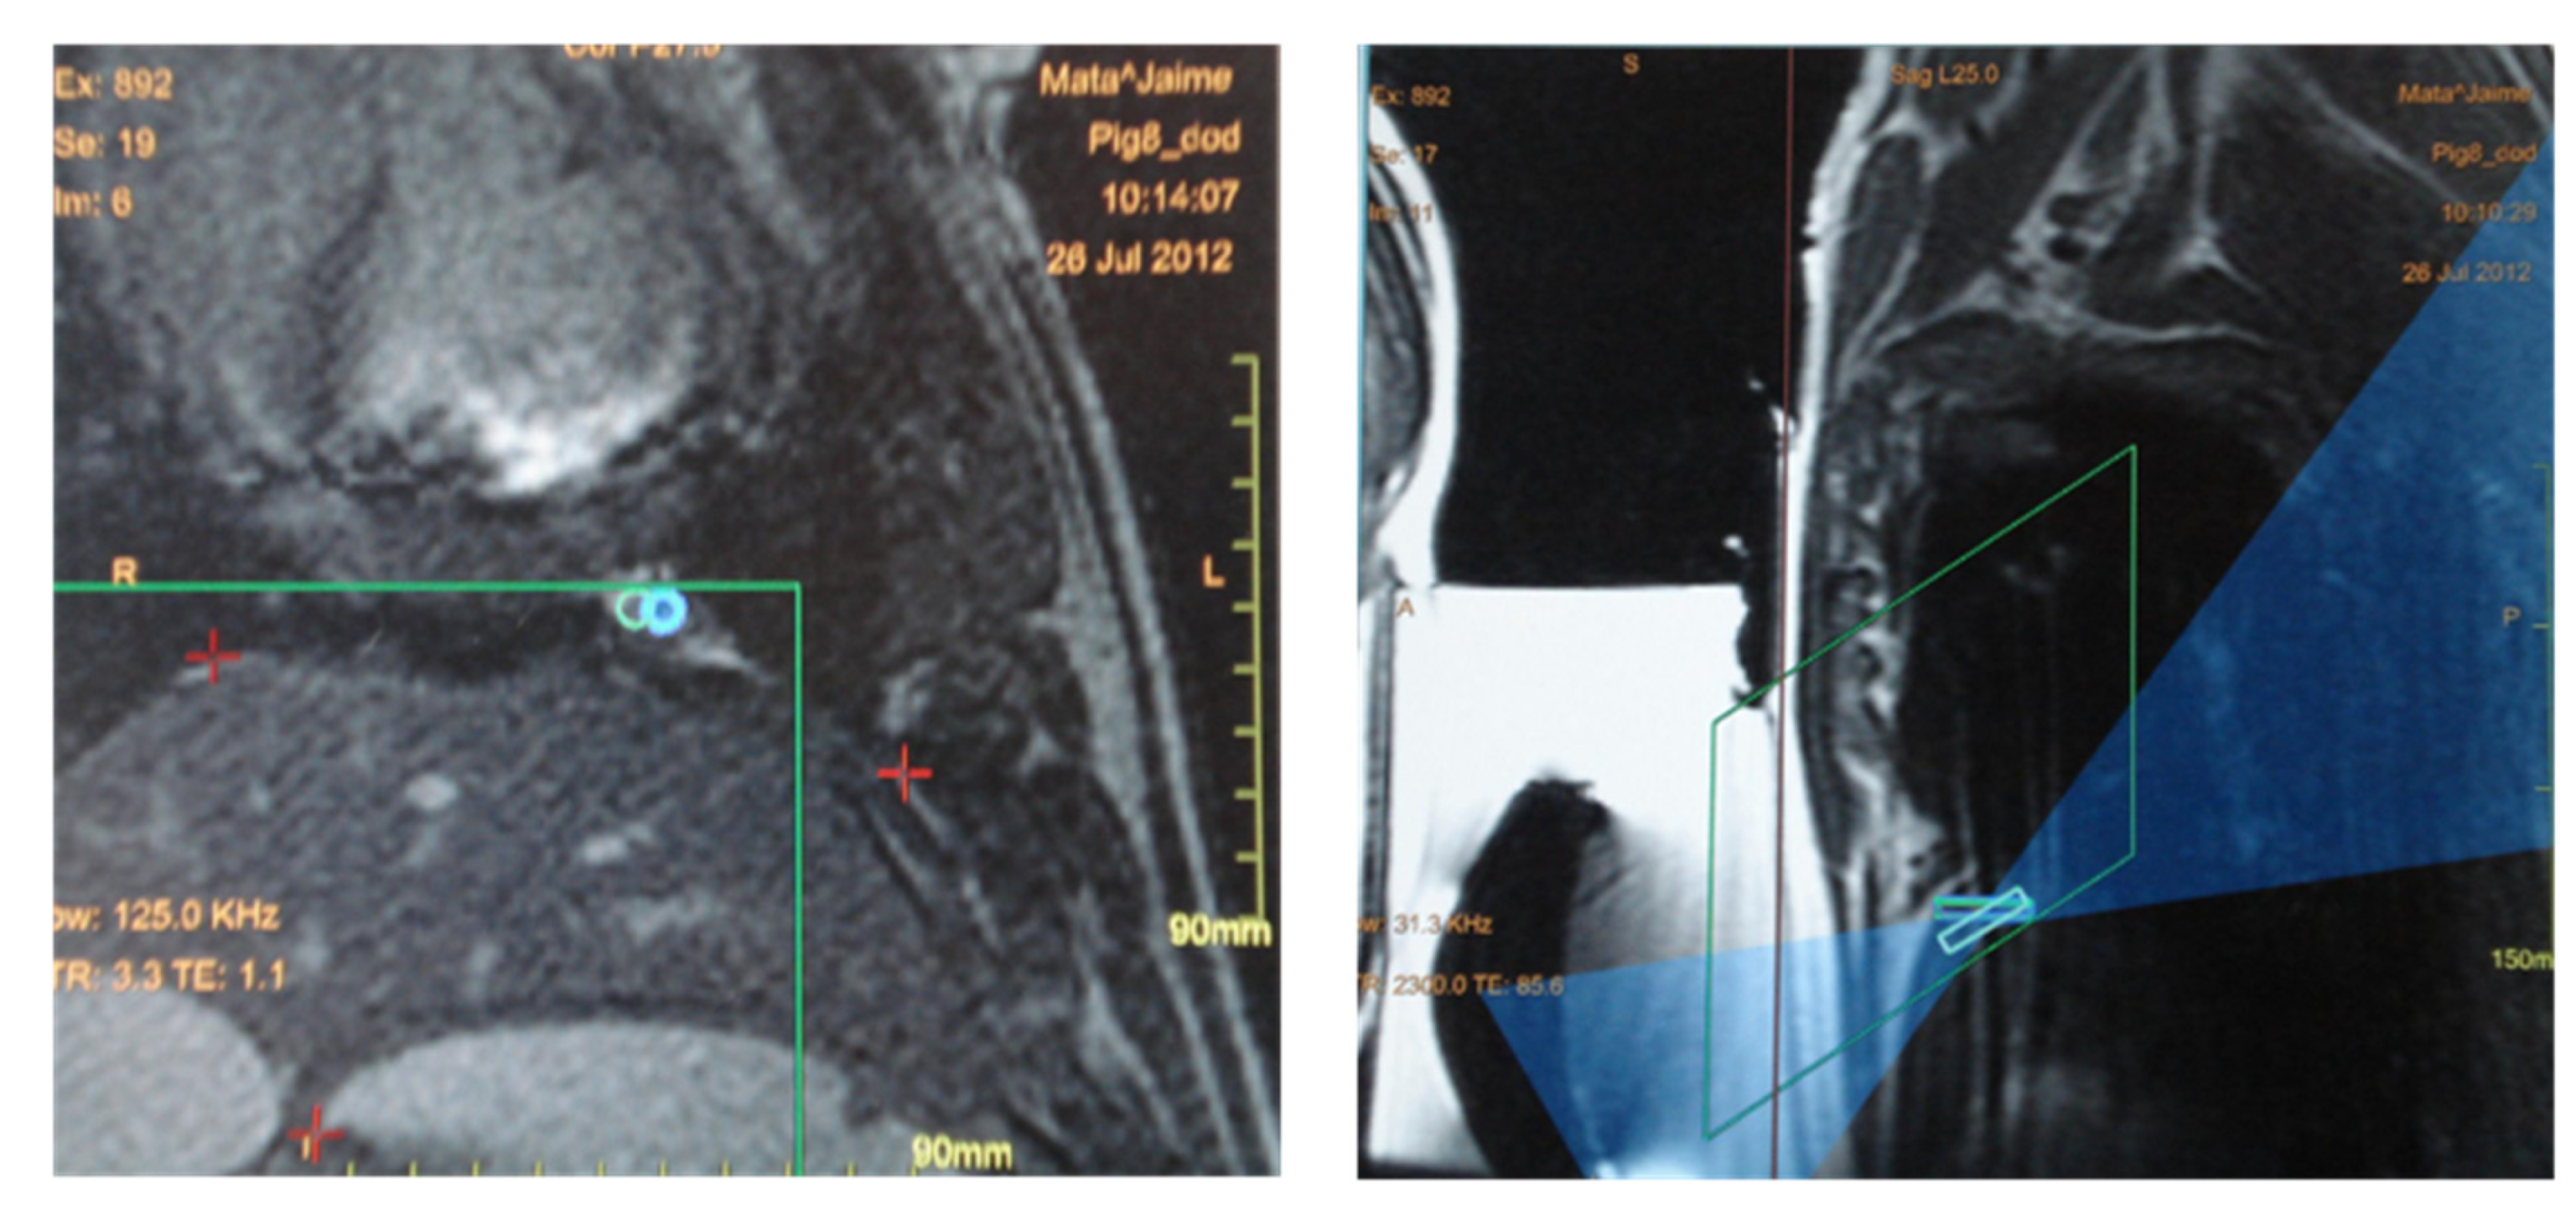

3.3. Magnetic-Resonance-Guided Focused Ultrasound